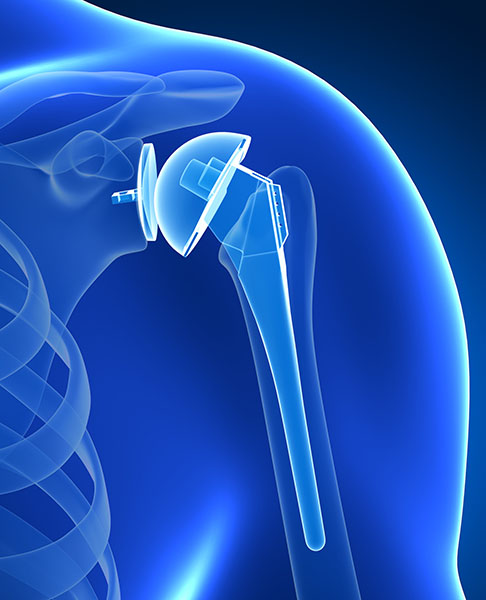

Shoulder Replacement

shoulder replacementThe shoulder joint is a ball and socket joint involving tendons, muscles, bones and ligaments. There is a smooth layer of cartilage on the socket (glenoid) and the round, ball-like part of the upper arm bone (humerus). This cartilage serves as a cushion and allows for smooth motion of the shoulder. Arthritis is the wearing away of this smooth cartilage, which eventually wears down to bone. The rubbing of bone against bone causes discomfort, swelling, stiffness and restriction of motion. When patients have failed conservative treatment such as rest, avoiding aggravating activities, medications, therapy, and cortisone injections, shoulder replacement may be offered.

There are different types of shoulder replacements available depending on your age and other factors. Our shoulder experts will carefully diagnose and explain your particular condition, and guide you to the most appreciate treatment.

Traditional shoulder replacement surgery involves replacing the damaged parts of the ball and socket joint with prosthetic materials. When the humeral head (ball side) alone is replaced, it is referred as a partial shoulder replacement. When the humeral head (ball side) and the glenoid (socket side) are both replaced, it is a total shoulder replacement. The humeral head is replaced with a metal prosthesis, which is attached to a stem, while the glenoid socket (if applicable) is replaced with a medical-grade plastic prosthesis. An intact rotator cuff is needed.

Reverse total shoulder replacement also replaces both the ball and socket but is performed when a patient has severe rotator cuff injuries that cannot be fixed. The goal of this procedure is to stabilize the damaged joint, as the problematic rotator cuff can no longer hold the humeral head in the glenoid socket. The surgeon will reverse the orientation of the shoulder’s ball and socket joint. The ball at the top of the humerus is removed, and it is replaced with a metal ball that is actually attached to the shoulder blade instead of the humerus. A prosthetic socket is attached to the top of the humerus, which is why this procedure is called a reverse shoulder replacement. This allows for better functionality due a deteriorated rotator cuff, pain relief and restoration of your independence.